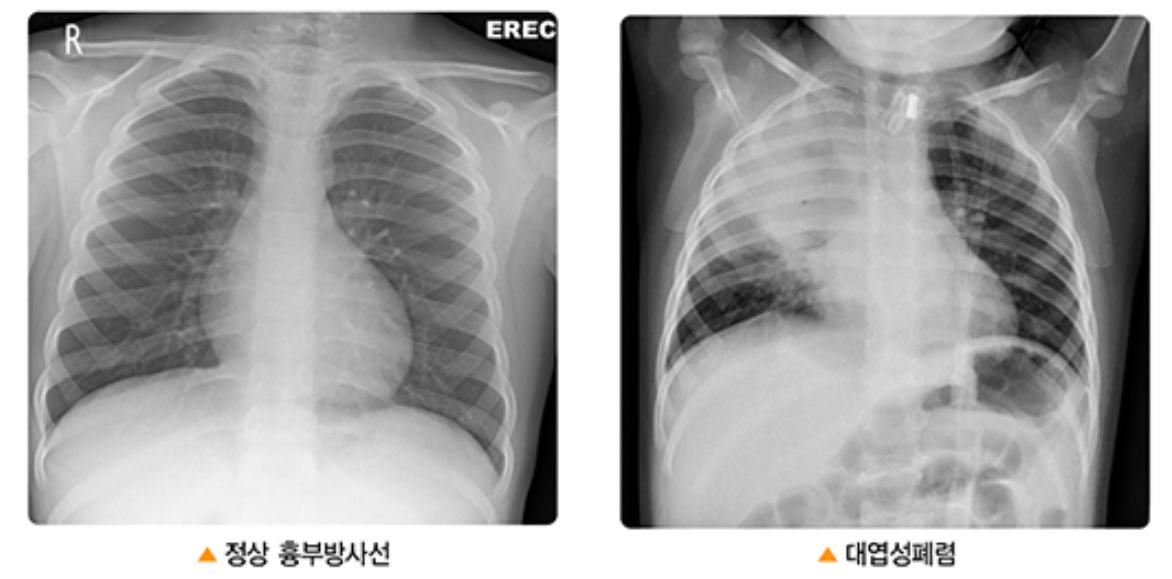

③ 흉부 엑스레이: 폐렴이 의심될 경우, 흉부 엑스레이를 통해 폐의 상태를 확인합니다. 엑스레이는 폐 염증의 범위와 위치를 파악하는 데 중요한 정보를 제공합니다.